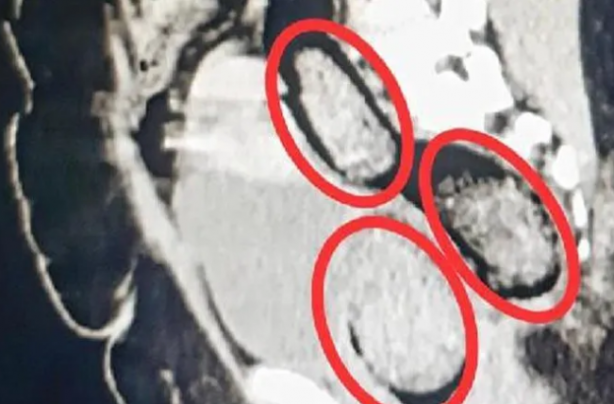

Hastanede çekilen röntgen sonucu makatında 3 parça uyuşturucu olduğu ortaya çıktı. Ekipler şaştı kaldı.

Kars Harakani Devlet Hastanesi'ne götürülen Aeınezad'ın çekilen röntgeninde, makatında uyuşturucu çıktı.

Cerrahi operasyonla kadının makatından 3 parça halinde toplam 318 gram metamfetamin çıkarıldı.